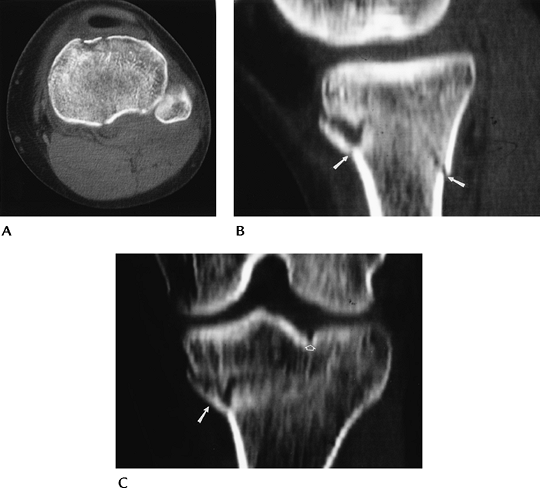

![]() |

FIGURE 5-10 CT images in the axial (A), sagittal (B), and coronal (C) planes demonstrating a minimally depressed fracture (arrows) with minimal articular displacement (open arrow).